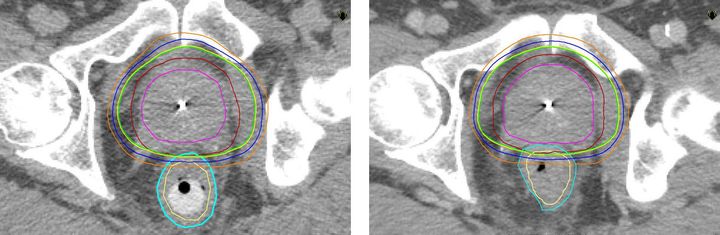

– Precis som vid annan strålterapi är målet med stavbehandling att döda cancercellerna. Vi behandlar 25-30 patienter per år med denna metod. Fördelen är att man kan öka avståndet mellan prostata och ändtarmen och därigenom ge högre stråldos i prostata och lägre i ändtarmen så att frisk vävnad skonas. Jämfört med konventionell strålbehandling utan rektalstav, som är vanligast idag, kan man ge lite högre stråldos utan fler biverkningar, säger Kristina Nilsson, överläkare i onkologi vid Akademiska sjukhuset.

Strålning är ett vanligt sätt att behandla prostatacancer, både när cancern är kvar i prostatan och när den spridit sig till andra delar av kroppen. Vid tidig sjukdom, när tumören inte spridit sig utanför prostatakörteln, är strålning ett likvärdigt alternativ till kirurgi som botande behandling. Forskning har visat att ju högre stråldoser man kan ge tumören, desto större är chansen till bot. De doser som fortfarande användes för något decennium sedan var ofta inte tillräckligt höga för att bota patienten. Det finns nu en stark strävan att utveckla metoder som gör att man kan öka stråldosen utan att förvärra biverkningarna.

* Rektalstaven förs in i ändtarmen som trycks nedåt och separeras från prostatan. På så sätt kan stråldosen minskas till ändtarmen.